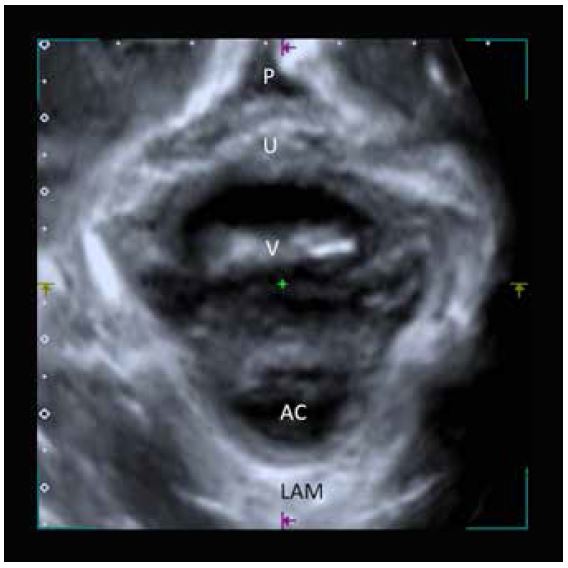

Малюнок 10. Площина мінімальних розмірів діафрагми. P: Лобок, U: Уретра, V: Піхва, AC: Анальний отвір, LAM: М'яз-підіймач відхідника